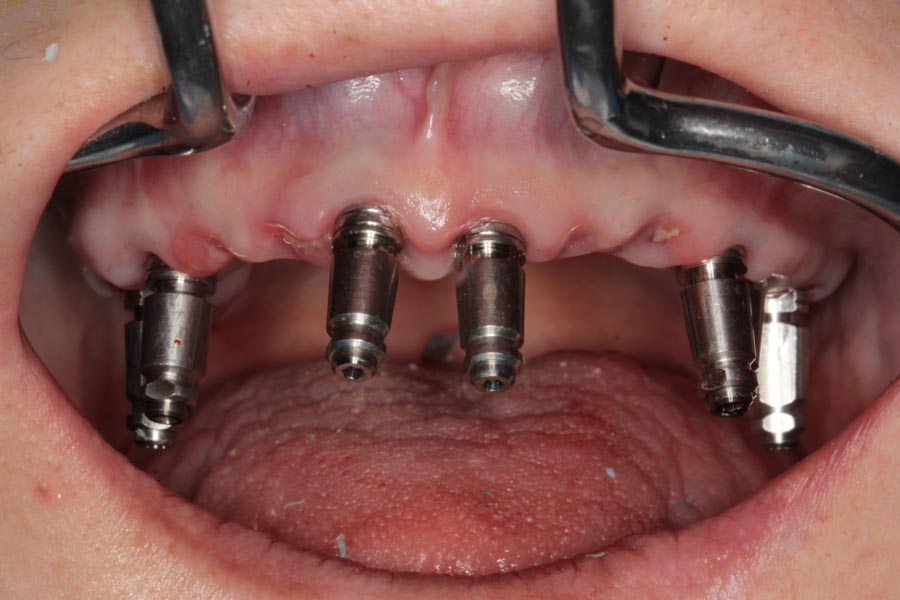

During the surgical appointment, all the teeth were extracted and implants were placed. The implants went in with sufficient torque/tightness so were able to make impressions and fabricate full-arch provisionals.

Provisionals were made here in our dental office and they were delivered on the day of surgery. Cleansable, convex forms were used to ensure the tissues can be shaped for maximum health and esthetics.